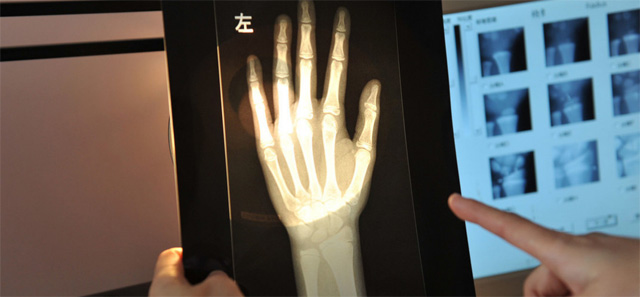

這個輻射到底對兒童有沒影響呢?其實影響不大的,預測孩子的骨齡是對身高的評估。怎樣監測,兒童在正常生長發育的過程中,隨著年齡的增加。骨骼線會逐漸的鈣化直至完全骨化,骨骼線閉合。骨齡是各個年齡骨的成熟度,正常情況下骨骼的年齡,和實際的年齡不應相差正負超過一歲。提前或者落后太多都是不正常的。用兒童的左手腕拍一張DR片來測骨齡,通過影像來觀測兒童骨骼生長發育情況。預測兒童的生長發育潛力。這個骨齡監測是比較準確的。

還有精準骨骼線檢查的位置在膝關節,通過DR拍片可以明確的看到骨骺線的狀態。這就是為什么檢查了手掌的骨骼線還有檢查膝關節的。手掌的骨骼線閉合了,也不一定代表不能生長了,通過精準的骨骼線檢查,判斷兒童是否有長高的可能。膝關節骨骼線未閉合就可以進行身高的干預治療。